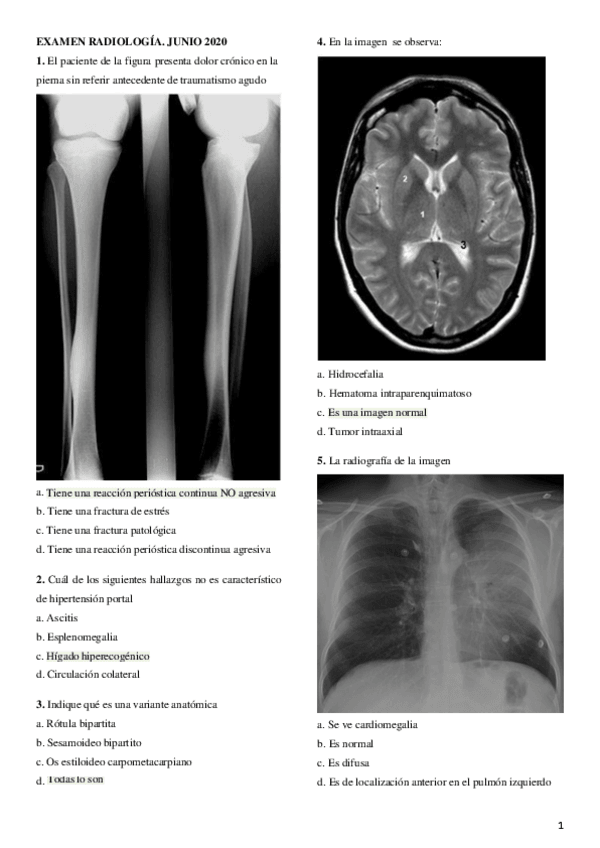

EXAMEN RAYOS ORDINARIA 2023

Dos archivos, uno con las preguntas y soluciones al final y otro con las imágenes que se han podido conseguir

EXAMEN-RAYOS-MAYO-2023-IMAGENES.pdf

EXAMEN-RAYOS-MAYO-2023.pdf